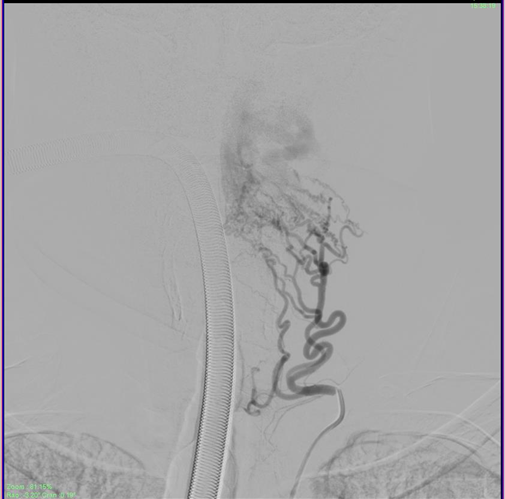

The sheath was then repositioned into the left Costocervical trunk. (The Echelon microcatheter was then advanced distally into the branch over a microwire (Figure 6). Multiple vials of Onyx were injected to the fistula achieving complete obliteration of the venous sac in just over 55 minutes approximately. The Onyx was also seen filling the adjacent feeder branches as well obliterating all arterial feeders to the EDAVF. A check angiogram of bilateral subclavian arteries and the right vertebral artery showed considerable slowing of flow into the EDAVF with approximately 80-90% obliteration of the venous sac (Figure 7).

Figure 6 Deep Cervical Feeders identified, after injecting the costocervical trunk.

Figure 7 Check angiogram showing complete obliteration of the compressive venous sac post embolization, and stasis in the draining veins which will eventually empty and close.

The Persistent Trigeminal artery maintained good flow in the vertebral artery allowing for good filling of the basilar artery and its vital branches (Figure 8). The Persistent Trigeminal Artery connect the anterior circulation directly to the basilar artery. Hence, damage to 1 or more vertebral arteries will not reduce blood flow to the brainstem. Hence these patents have a high tolerance for vertebral artery manipulation and even thrombosis. The procedure was stopped, and the patient was extubated. Post op he was deficet free, alert conscious and content. The femoral sheath was removed the next day, and the patient was mobilized and discharged after 2 days. He has review in OPD after 3 months and repeat angiographic investigations have showed no filling in the EDAVF ever since.